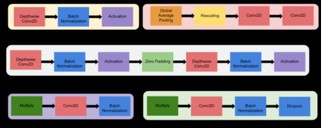

Feature Extraction Process using CNN algorithm includes convolutional layers, depthwise and pointwise separable convolution and Class Active Mapping (CAM).

1. Convolutional layers: They facilitate the MRI’s local feature extraction. It can distinguish edges, textures, and other regional patterns that are essential for diagnosing the brain alterations associated with AD.

2. Depth wise separable convolutions: They use fewer parameters and require fewer computing costs. By splitting the convolution operation into depthwise and pointwise convolutions, it is able to extract more abstract features.

C. EfficientNetB2: Algorithm—Efficient Net-B2 is trained for classification in the standard manner. EfficientNet-B2 is a specific variant of the EfficientNet family of neural network architectures [21]. Mingxing Tan and Quoc V. Le proposed the EfficientNet models in their paper “EfficientNet: Rethinking Model Scaling for Convolutional Neural Networks” in 2019. This model provides better performance and efficiency by depth scaling, width scaling, and resolution scaling of the network in a balanced way. EfficientNet is relatively consistent with near perfect training curves and provides less loss and Peak accuracy about 97.22%. figure.11 explains the modules of the EfficientNetB0.